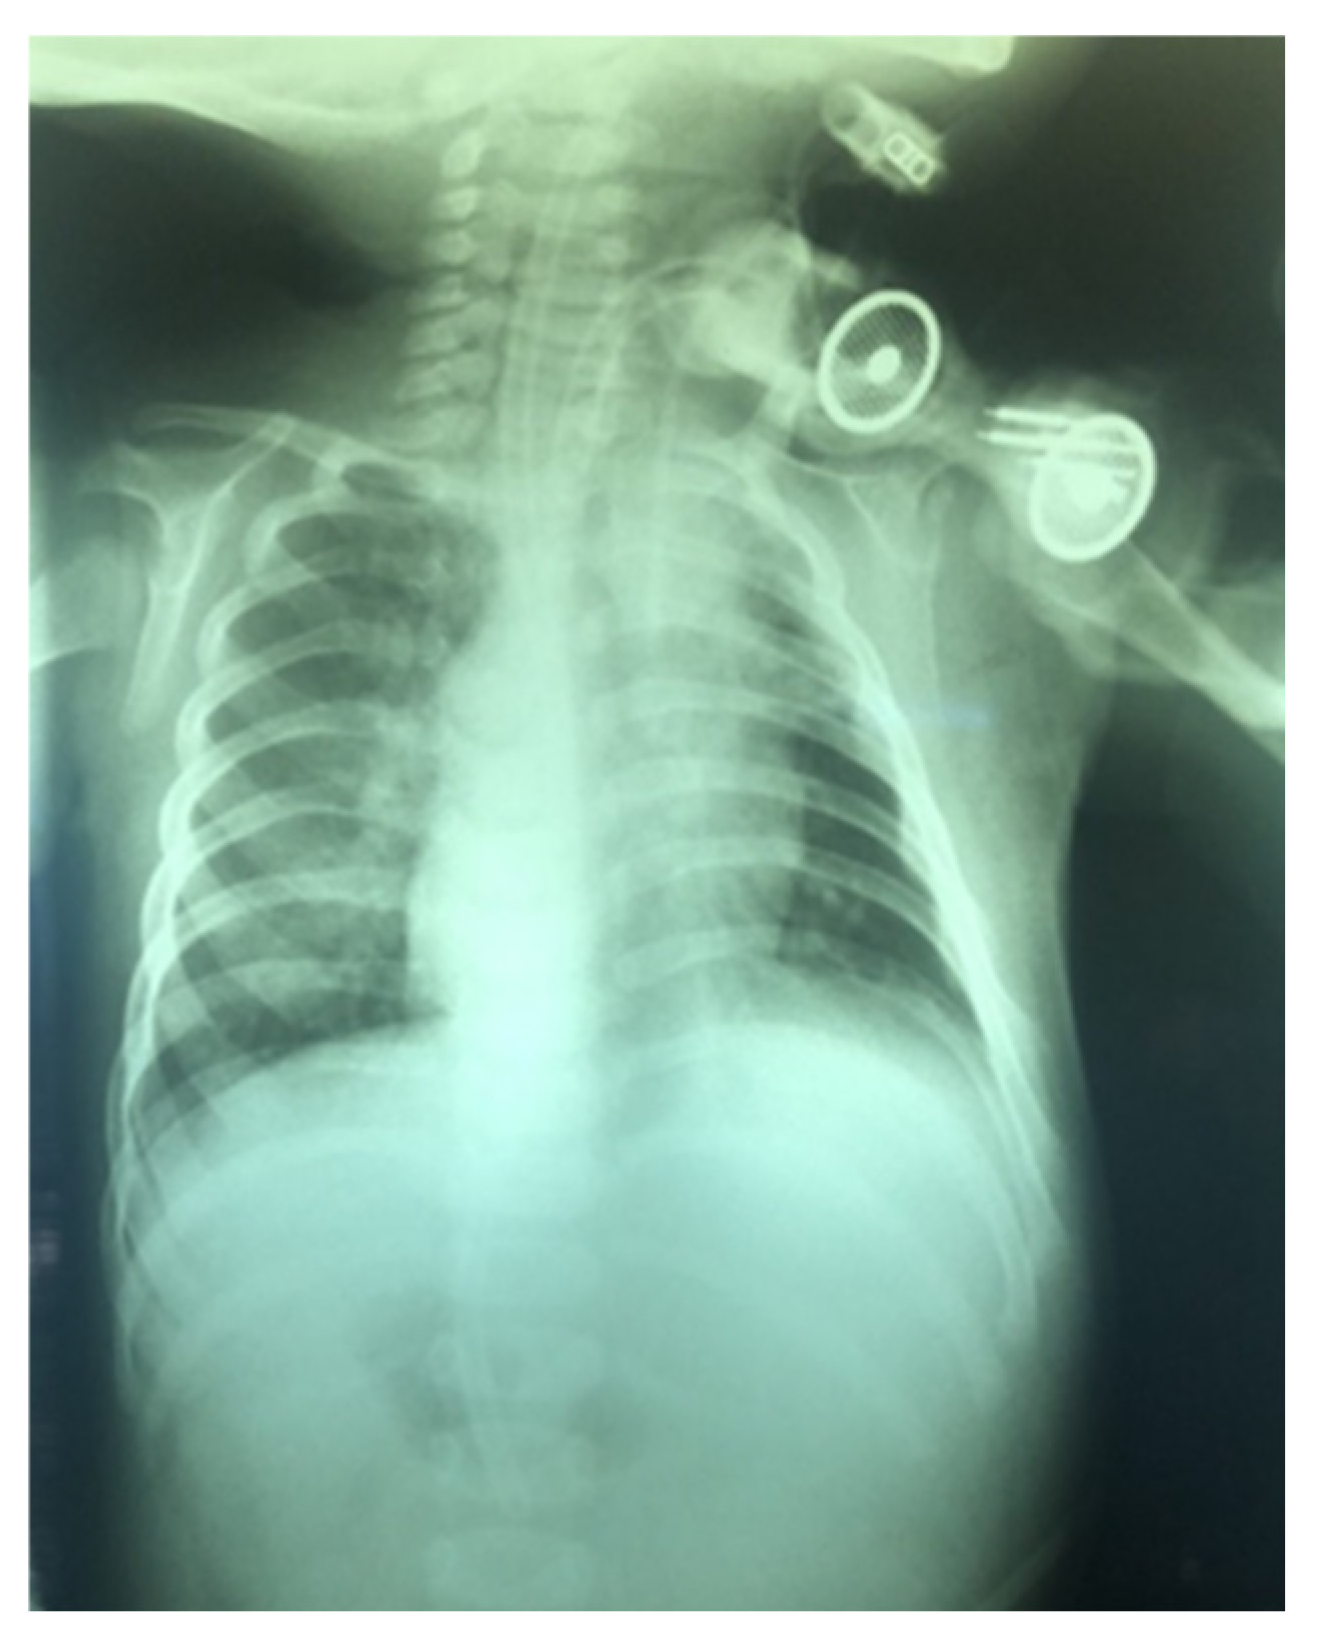

- If stay sutures have been placed on the trachea, they are secured to the patient’s chest and are clearly labeled as “left” and “right.” (Figure 8). These sutures are typically removed during the first or second cannula changes.